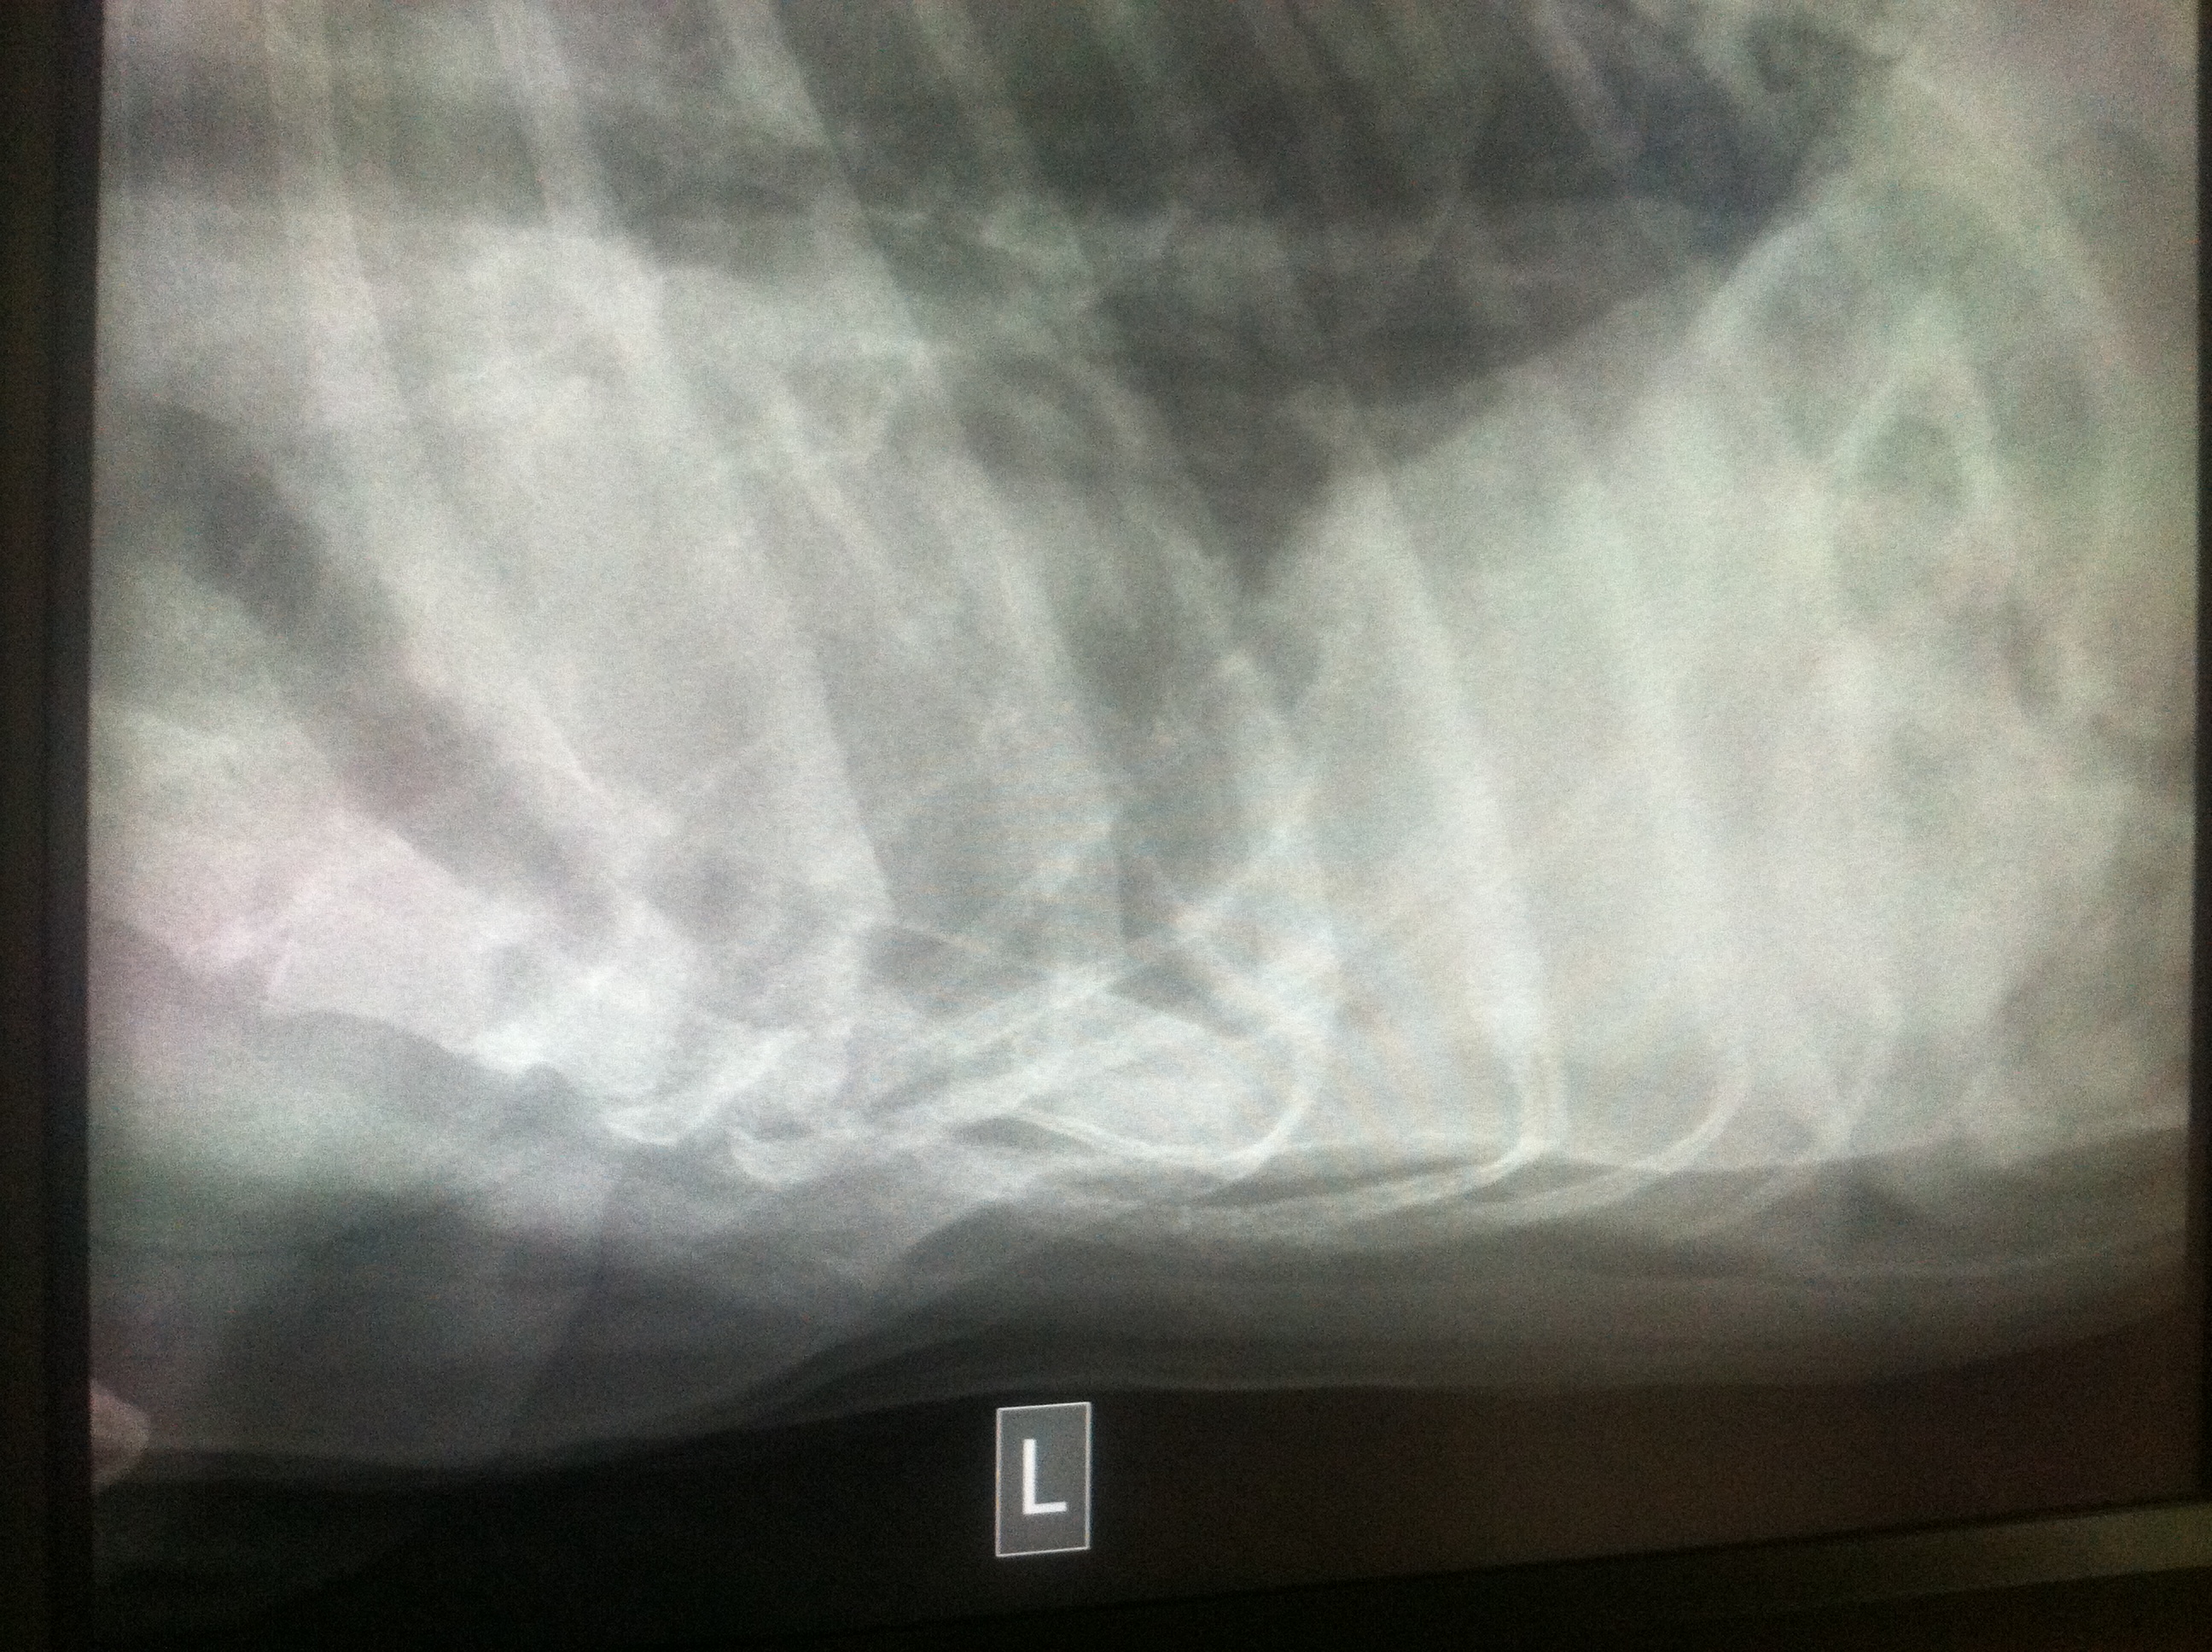

I took some pictures of Sherman’s x-rays over the past month so you can see the difference in his chest.

(these are pictures of the chest x-rays that I took from my iPhone. I was too lazy to upload them to a disc so they did lose some of their clarity)

I am not going to act like I know a lot about what these x-rays are showing because reading x-rays is not my forte, but I can tell you what was explained to me:

Pleural effusions appear on chest X-rays as white space at the base of the lung. Pleural effusion obscures the silhouette of the heart

It’s really hard to see Sherman’s lung in these small pictures but you can see the white space in the top two pictures and his heart has obvious loss of details compared to the 3rd x-ray.

Pnuemothorax means air in the chest cavity.

In the first 2 pictures there is mild pneumothorax in Sherman’s chest cavity.

Again, it’s hard to see in these pictures. Taking x-rays of the chest of a giant breed dog is no easy task. The x-rays plates just aren’t big enough to accommodate them.